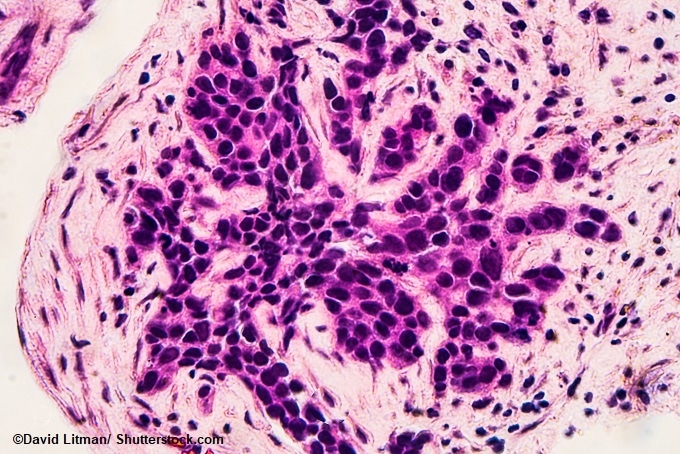

Image: Photomicrograph of core biopsy for infiltrating (invasive) ductal carcinoma, detected by screening mammogram. H & E stain.

In the study, published today in the Journal of the National Cancer Institute, the researchers used immune cell ‘hotspots’ in and around the tumors able to predict a women’s likelihood of breast cancer relapse. They found that women who possessed a large number of hotspots were more prone to relapse when compared with women who had less hotspots.

The results showed that, in comparison with the immune cells that are equally dispersed in the hotspots, the chance of recurrence within a period of 10 years from the start of the treatment was 25% higher when the immune cells were clustered together. Also, in women with immune cell hotspots, the chance of re-occurrence of the cancer within the duration of 5 years was 23% higher.